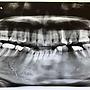

我左下第一大臼齒根管治療、裝牙套超過十年以上,同時間也拔除左下第二小臼齒。. 拔牙原因忘了,疑似因蛀牙及生長空間不足。. 上週因牙齦腫脹,醫生評估建議將牙套拆除檢查。檢查後,建議拔牙。(目前牙齒還沒拔)

https://i.imgur.com/siOrJes.jpg.

醫生測量第一小臼齒與第二大臼齒間